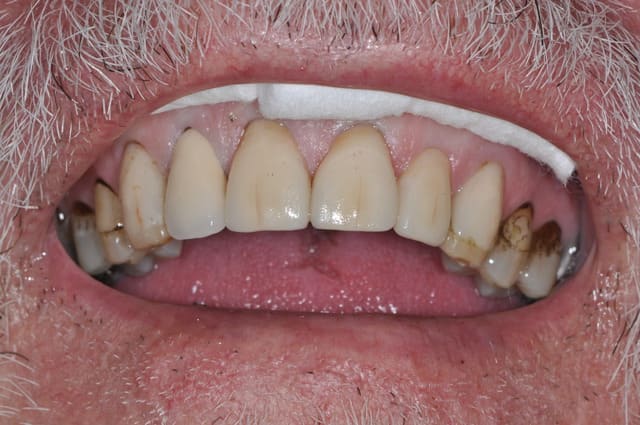

Bonjour,

savez-vous quelle est la raison de cette porosité de surface ?

il s'agit d'emax sur 11 21 22.

non en fait ma question porte sur l'état de surface de mes emax,

la coloration est présente depuis un bon moment et je n'en connais pas l'origine

je joins une photo avant traitement